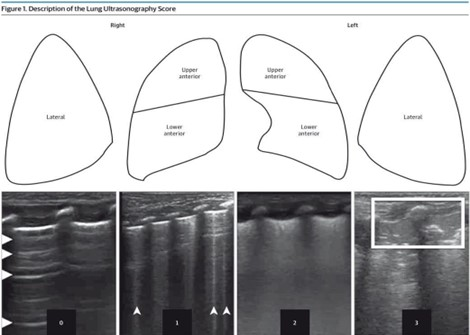

There is growing evidence that lung ultrasound scoring can be used to measure the risk of developing bronchopulmonary dysplasia. Poor respiratory outcomes and frequent respiratory exacerbations are common complications of preterm birth. The researchers however noted a lack of data tying the use of lung ultrasound with later respiratory outcomes.

Bonadies and colleagues studied the association between lung ultrasound within the first three, seven, and 14 days of life, and respiratory outcomes at 2 years corrected age. Outcomes included respiratory exacerbations, physician-diagnosed wheezing episodes, and respiratory medication use.